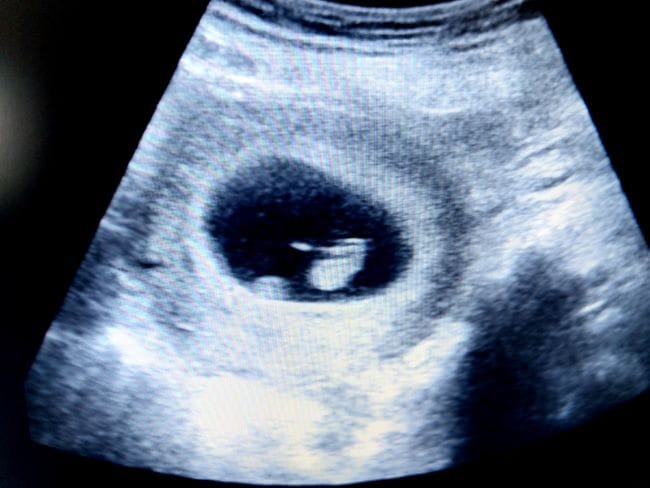

Janin 6 minggu menandakan bahwa kandungan Bunda telah berada di pertengahan trimester pertama, tepatnya di bulan kedua. Pada usia ini, ukuran janin masih sangat kecil, yaitu sekitar 0,5 cm atau seukuran kacang lentil dengan kepala dan ekor besar layaknya kecebong. Meski begitu, ukuran ini sudah bertambah dua kali lipat dari minggu sebelumnya lho, Bun.

Walau belum berkembang dengan sempurna, jantung janin 6 minggu sudah mulai berdetak lho. Bahkan, Bunda dapat mendengarnya saat melakukan USG, terutama USG transvaginal.